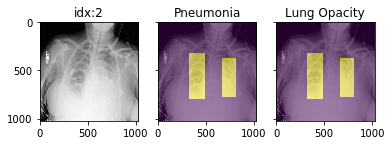

Pathology masks (demo notebook)

Masks are available in the following datasets:

xrv.datasets.RSNA_Pneumonia_Dataset() # for Lung Opacity

xrv.datasets.SIIM_Pneumothorax_Dataset() # for Pneumothorax

xrv.datasets.NIH_Dataset() # for Cardiomegaly, Mass, Effusion, ...

Example usage:

d_rsna = xrv.datasets.RSNA_Pneumonia_Dataset(imgpath="stage_2_train_images_jpg",

views=["PA","AP"],

pathology_masks=True)

# The has_masks column will let you know if any masks exist for that sample

d_rsna.csv.has_masks.value_counts()

False    20672

True      6012

# Each sample will have a pathology_masks dictionary where the index

# of each pathology will correspond to a mask of that pathology (if it exists).

# There may be more than one mask per sample. But only one per pathology.

sample["pathology_masks"][d_rsna.pathologies.index("Lung Opacity")]